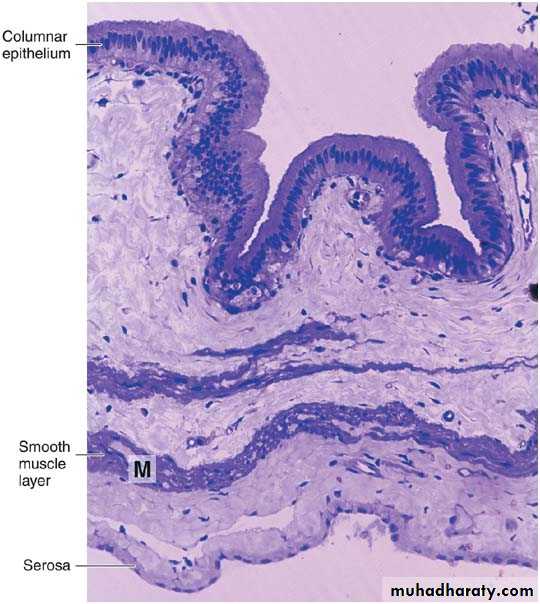

• Photomicrograph of a section of gallbladder. Note the lining of columnar epithelium and the smooth muscle layer (M). PT stain. Low magnification.